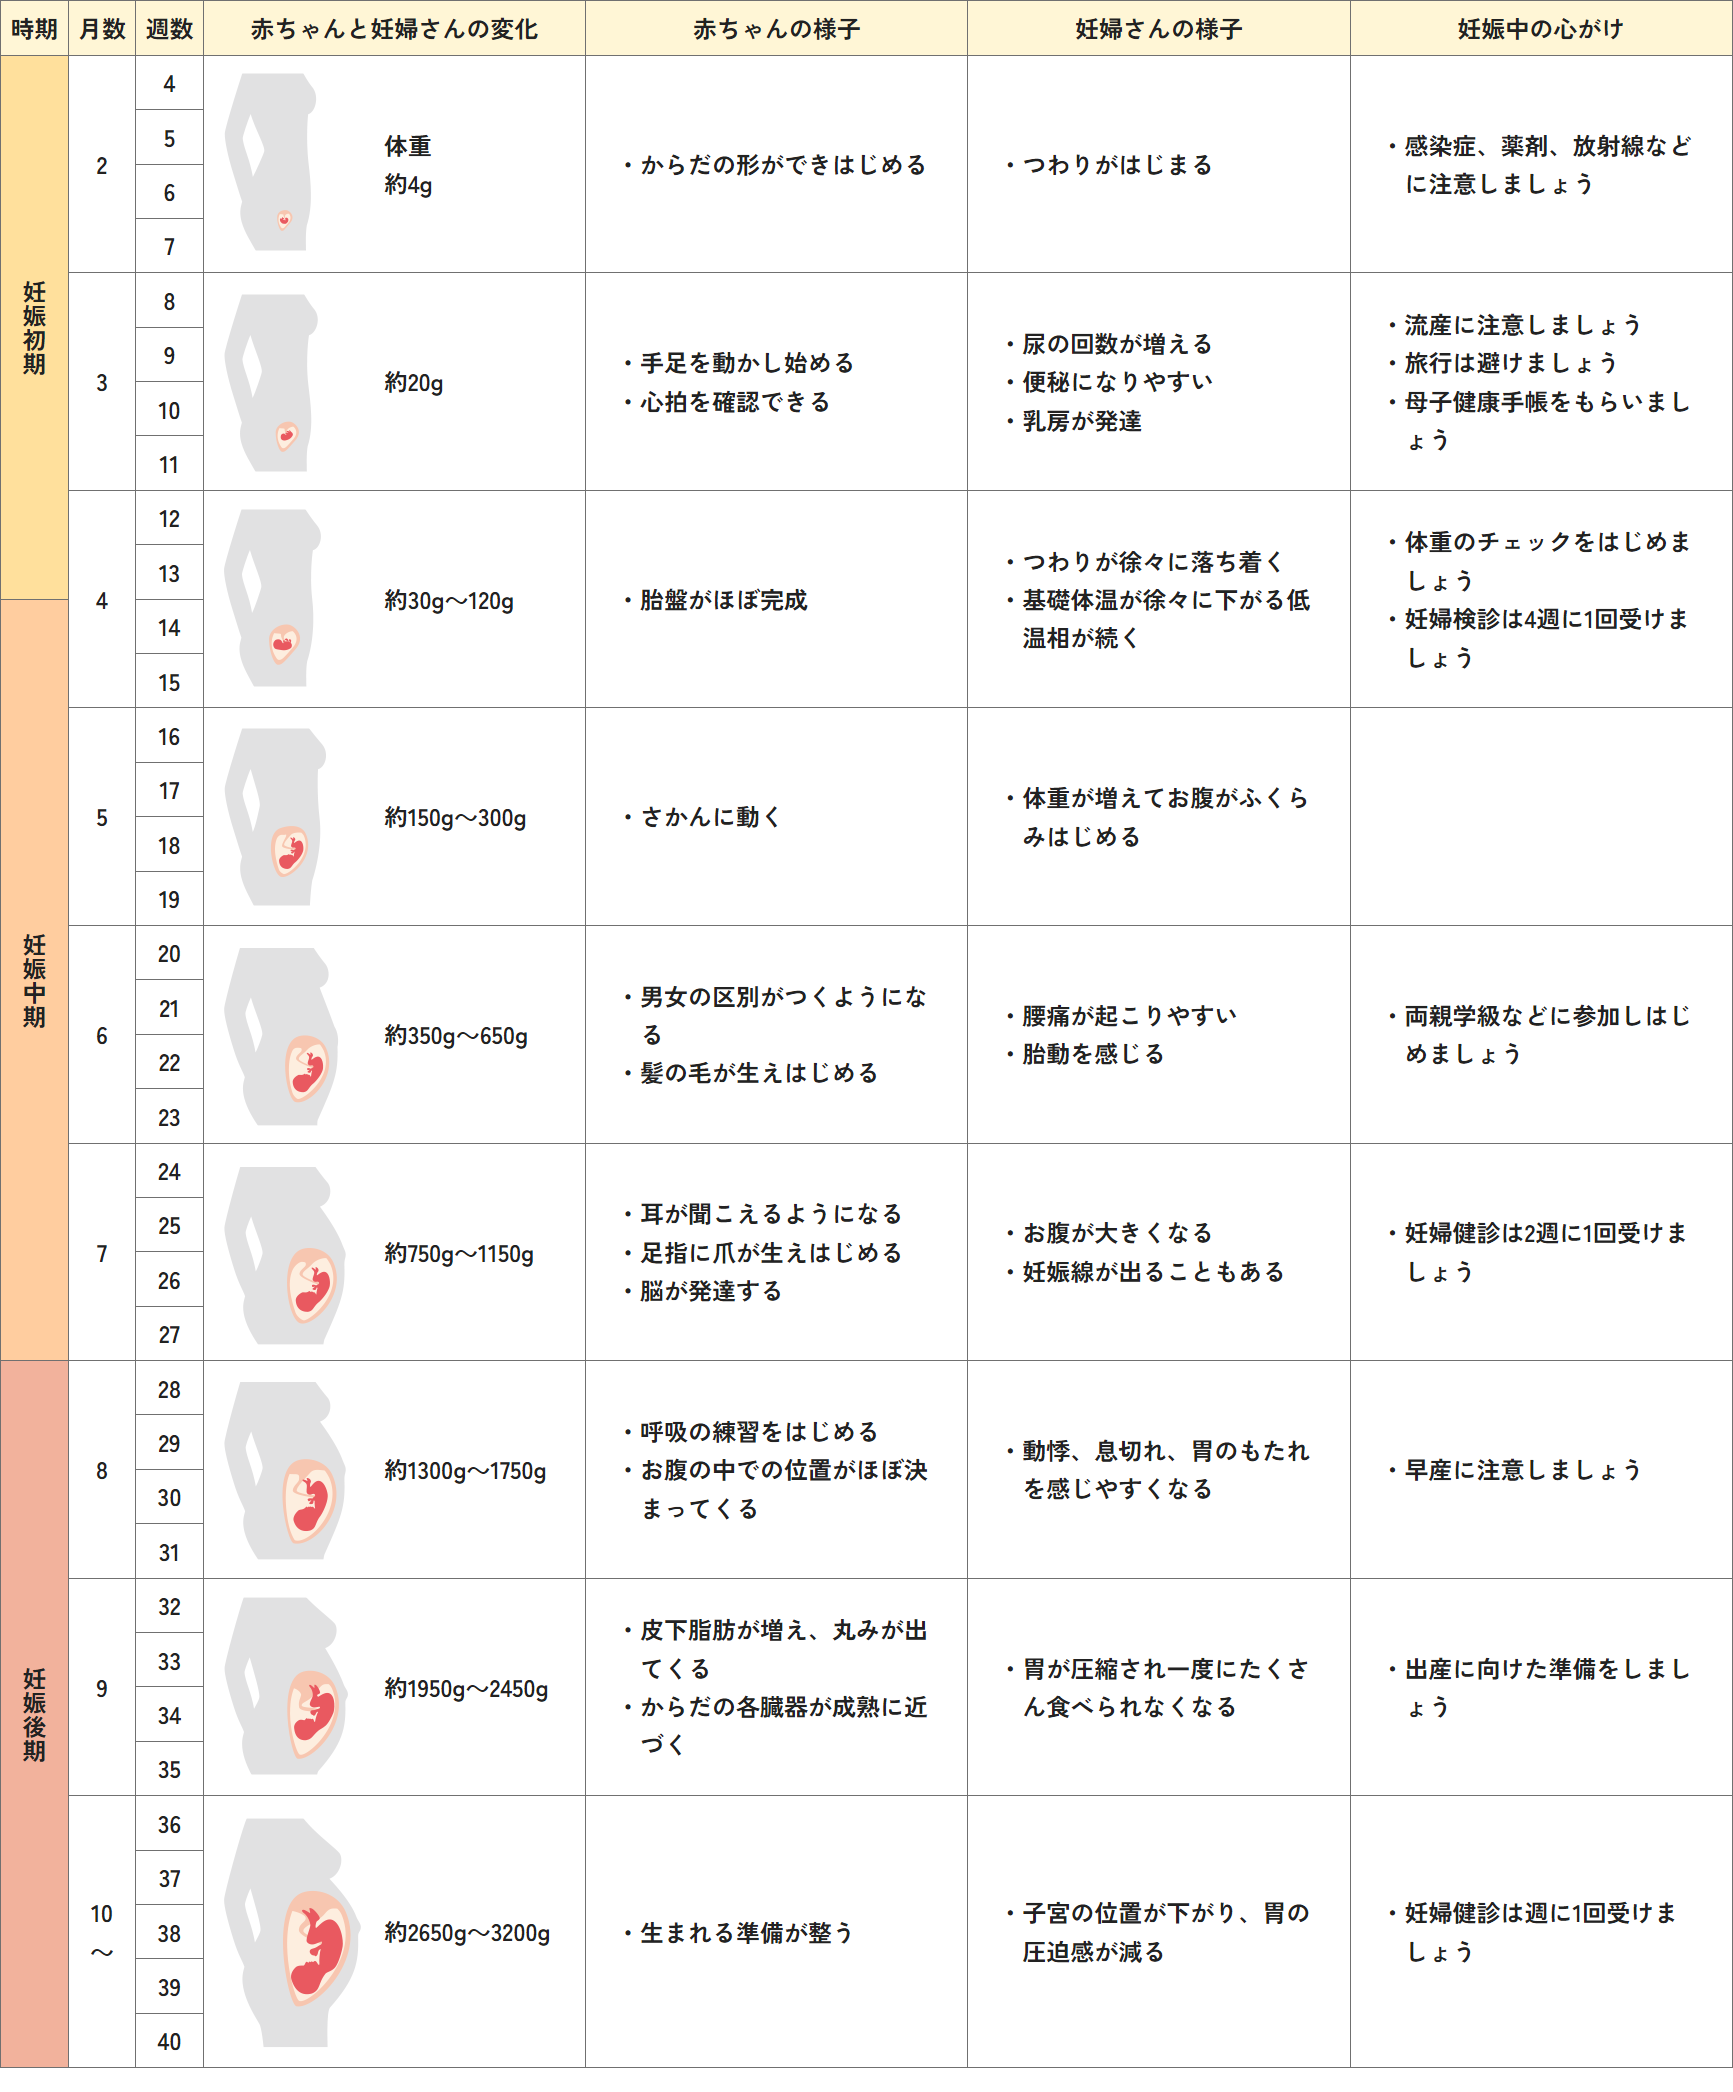

母子手帳「胎児発育曲線 新生児の成長曲線 」の見方と活用法-おむつのムーニー 公式 ユニ・チャーム。

医師監修 胎児の発育曲線 成長曲線 とは?どのように見ればいいの?ゼクシィBaby。

胎児発育曲線ギリギリ成長の小ささで16週から34週まで育ってるべびお君。 - 保育士うたのサイト。

胎児発育曲線』とは?週ごとの発育の目安を助産師が解説◎ - 株式会社エバーセンス。

胎児発育曲線』とは?週ごとの発育の目安を助産師が解説◎ - 株式会社エバーセンス。

胎児発育曲線の±2.0SDの意味は?エコー写真に学ぶ統計学 - 日常を少し掘り下げてみる。

医師監修 おなかの赤ちゃんの発育は順調? 「胎児発育曲線」とはトモニテ。

胎児発育曲線の±2.0SDの意味は?エコー写真に学ぶ統計学 - 日常を少し掘り下げてみる。

母子手帳「胎児発育曲線 新生児の成長曲線 」の見方と活用法-おむつのムーニー 公式 ユニ・チャーム。